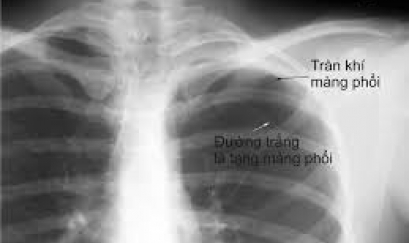

Thông tin cần biết về giãn phế quản sau lao